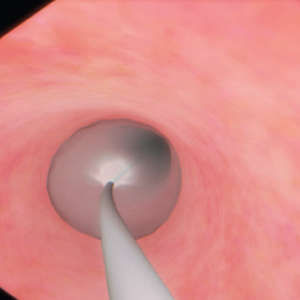

Real-feel surgical simulation. Diagnostic and surgical skills in Endoscopy

EndoVision sets the standard in simulation for hands-on-training in endoscopic procedures. Allowing trainees realistic and safe clinical experiences

EndoVision offers exposure to an extensive library of modules and patient cases to challenge diagnostic and psychomotor skills in preparation for real presentations.

High-precision no-lag instrument tracking system provides accurate, smooth response for all your actions.